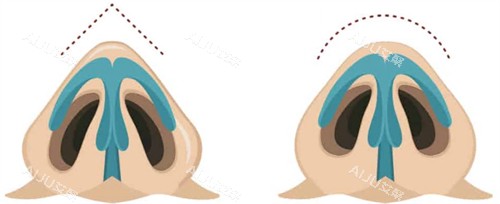

鼻整形曹海峰在南京哪个医院坐诊呀?鼻整形医师曹海峰医生目前坐诊于南京施尔美整形医院,以其优质的隆鼻及鼻修复技术赢得了稳定的好口碑。

杨万忠医生凭借二十多年的执业生涯和对鼻整形技术的深入研究,在业内树立了良好的口碑。他擅长多种鼻整形技术,尤其是肋骨鼻等自体软骨隆鼻手术,能够根据个人的脸型和形象设计出适合的鼻形方案。现在,想要预约杨万忠医生进行鼻整形的朋友可以通过公众号、线上平台或电话轻松预约,开启您的美丽之旅。